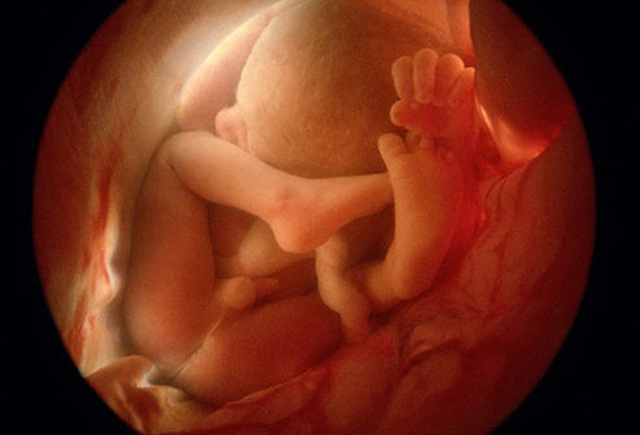

Semana 29

El bebé se coloca para nacer. Es el momento óptimo, ya que hay suficiente espacio en el útero y líquido amniótico para que el bebé se mueva con soltura, porque en unas pocas semanas el feto empezará a engordar y el útero se convierte en un espacio cada vez más reducido para hacer piruetas.

El cerebro se vuelve más irregular con acanaladuras y hendiduras, resultado de las conexiones que las células nerviosas, le permiten realizar nuevas actividades cerebrales, como dormir.